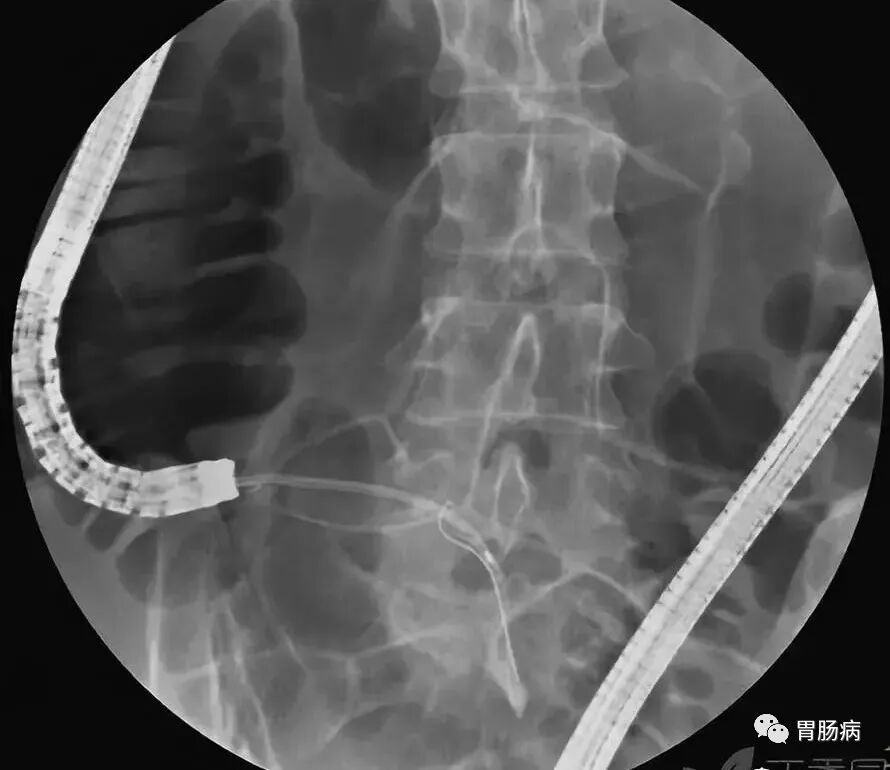

2.内镜逆行性阑尾造影术(endoscopic retrograde appendicography,ERA):

X线下,阑尾腔内注入造影剂显示阑尾腔的形态(椭圆形线圈),如有粪石(黑箭头),则行球囊取石术。并确认有无阑尾穿孔。